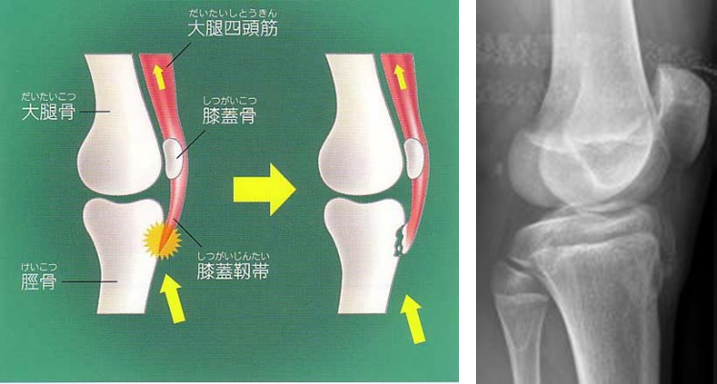

病因

胫骨结节骨骺未融合,衔接薄弱,容易受到损伤。当进行跑、跳、踢等剧烈运动时,股四头肌长期、猛烈收缩,可使髌韧带反复牵拉附着处的胫骨结节,致结节软骨慢性损伤,引起创伤性炎症和修复性反应,造成胫骨结节炎和局部隆起。

影像学表现

一、X线

1.早期表现为局部软组织肿胀,髌韧带增粗肥厚显著,继之则产生肌腱的钙化和骨化,胫骨结节呈舌状隆突,密度增高、碎裂,且与骨干轻度分离,形成大小、形态不一的骨碎块。

2.分离部位的骨骺边缘可见小的裂隙状缺损。

3.骨骺修复后胫骨结节可恢复正常或略有增高隆起,但常可留下分离的碎骨块,至成年时为胫骨结节上方的游离体,长期游离于髌韧带内。